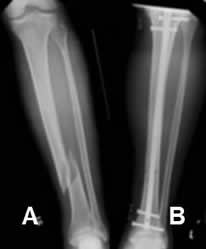

A: Rx AP. Fractura espiroidea en la tibia distal.

B: Rx AP. Reducción anatómica y estabilización con clavo de Kuntcher.